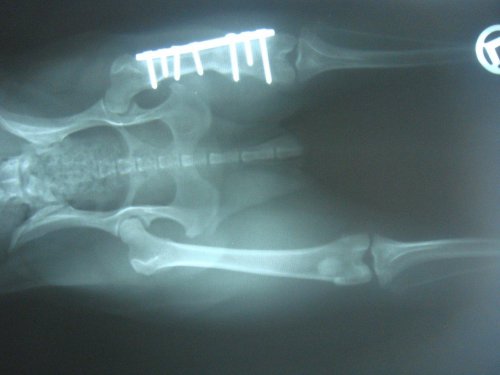

Alle Welpen wurden vermittelt und Tilly wurde am 21.12.2012 bei Dr. Rumpf operiert. Sie hatte einen alten Oberschenkelbruch im linken Hinterbein.

Die OP ist gut verlaufen, Tilly hat eine Platte bekommen und muss im September 2013 nochmals operiert werden. Dabei wird die Platte dann wieder entfernt.

Da der Bruch vermutlich schon mind. ein halbes Jahr alt war, musste bei der OP bei beiden Knochenenden 1,5 cm abgeschnitten werden. Dadurch ist ihr linkes Hinterbein nun verkürzt und Tilly wird immer humpeln. Aber mittlerweile verwendet sie ihr Bein schon wieder mehr.

Ein Kontrollröngten im Jänner 2013 zeigte, das alles in Ordnung ist.

Tilly wurde am 19.2.2013 kastriert und da haben wir nochmal ein Kontrollröntgen machen lassen. Auf diesem Foto kann man sehr gut erkennen, dass der Knochen kürzer ist.